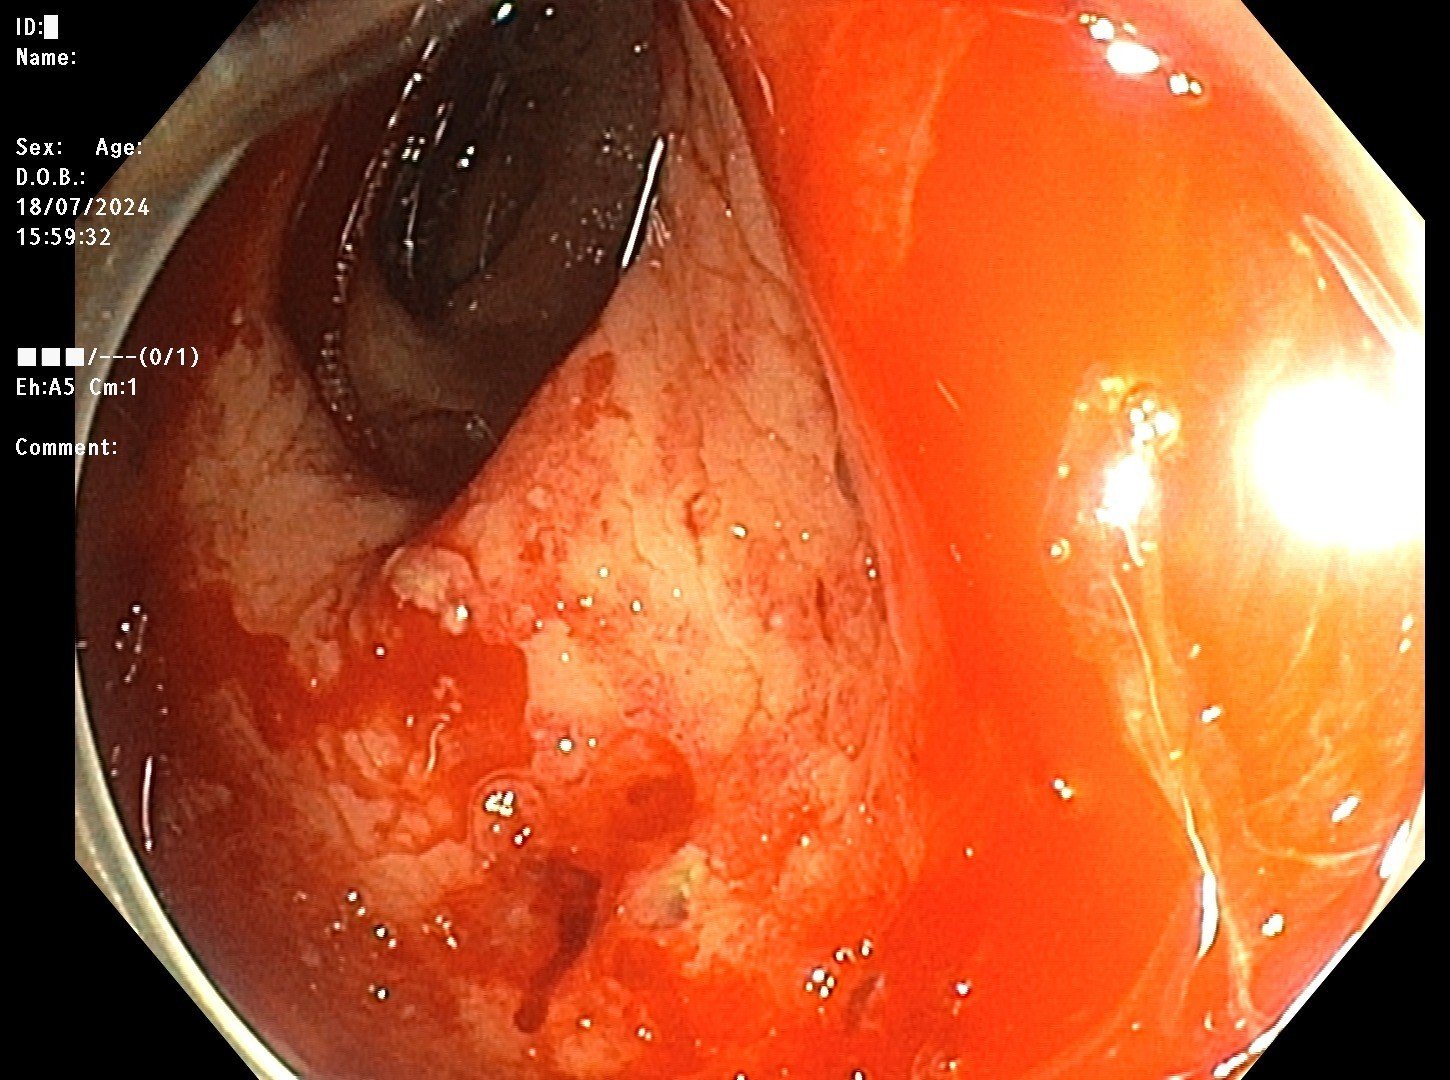

- Hình ảnh trước can thiệp

1 tuần nay bệnh nhân nữ, 59 tuổi mệt mỏi, hoa mắt chóng mặt khi đi lại, đại tiện phân máu đỏ, máu thẫm thành đợt và có tiền sử ung thư cổ tử cung đang xạ trị, hóa chất, đã từng phải truyền máu 2 tháng trước đó. Tiếp nhận người bệnh tại Bệnh viện đa khoa Quốc tế Hải Phòng, qua thăm khám và nội soi kết quả cho thấy, bệnh nhân viêm niêm mạc đại trực tràng do tia xạ, chảy máu.

Nhận định đây chính là nguyên nhân khiến bệnh nhân thiếu máu nặng, đại tiện phân máu trong suốt thời gian vừa qua, người bệnh cần phải truyền máu và can thiệp cầm máu kịp thời, tránh mất máu nhiều nguy hiểm đến tính mạng. Tuy nhiên, không thể cầm máu bằng cách thông thường như kẹp hay chích cầm máu do giãn mao mạch, các mao mạch đang chảy máu, bác sĩ Khoa Tiêu hóa – Nội soi, Bệnh viện đa khoa Quốc tế Hải Phòng đã quyết định sử dụng phương pháp nội soi can thiệp cầm máu, đốt Argon Plasma vào các vị trí mạch máu loạn sản đồng thời truyền máu kịp thời cho người bệnh.